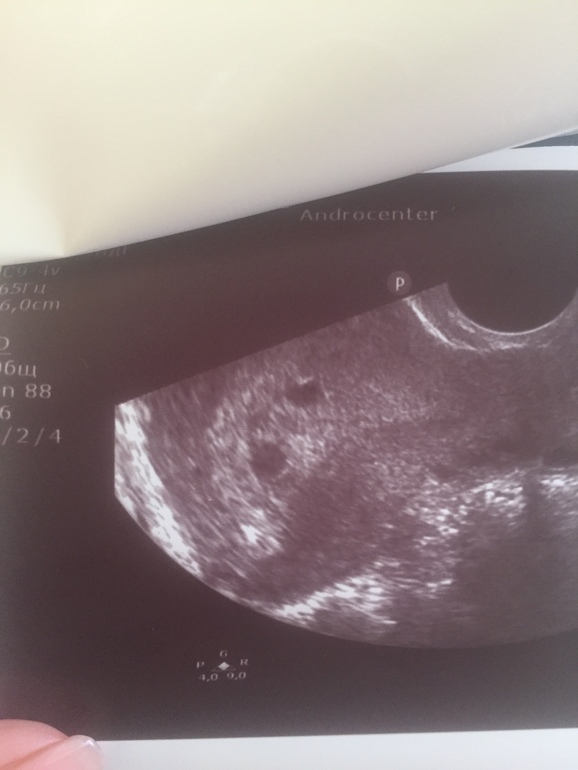

.узи сегодня

Только что вернулась с узи. Врач больше часа смотрела на аппарате. Я сразу не говорила что мне поставили ПЗ под вопросом два дня назад. Но почти сразу врач стала очень насторожена и тщательно рассматривала. Ее мнение - пришла я очень рано и что то конкретное глвлрить сложно. Плодное яйцо есть, но рядом есть еще что-то. На ее аппарате назвать структуру множественной нельзя. На второе плодное ни по форме ни по контуру не похоже. Желтое тело одно в правом яичнике. Левый вообще прижат к матке (возможно спайки). На кисту или отслойку не похоже (нет гематомы). Я потом уже сказада что это второе узи на другом аппарате. Врач внимательно рассматривала чтоб исключить Пузырный, но говорит что он выглядит по другому но есть вероятность что просто рано и он еще может развиться. поставила тоже пузырный под вопросом.